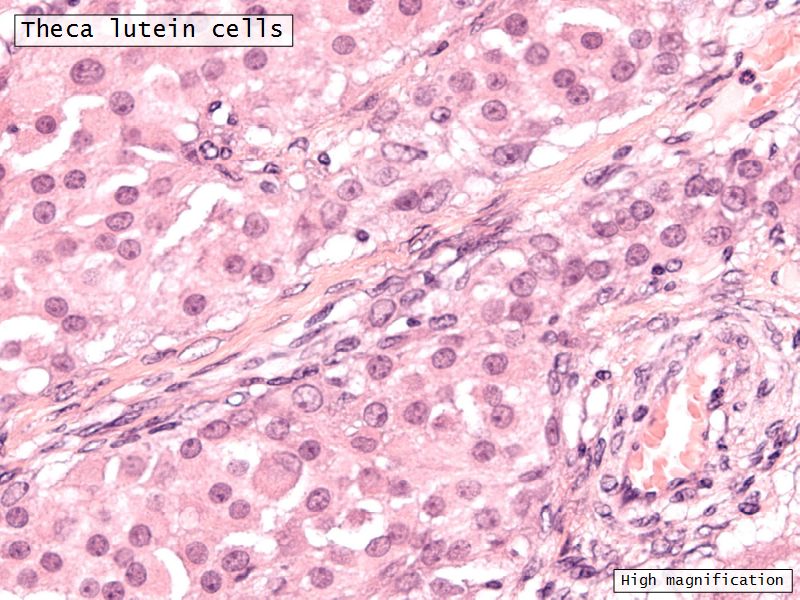

Theca lutein cells

- Modified theca interna cells

- Smaller - 15µm

- Dark stained